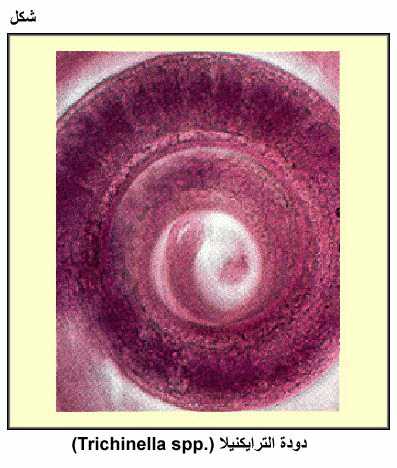

دودة الترايكنيلا

دودة الترايكنيلا (.Trichinella spp)